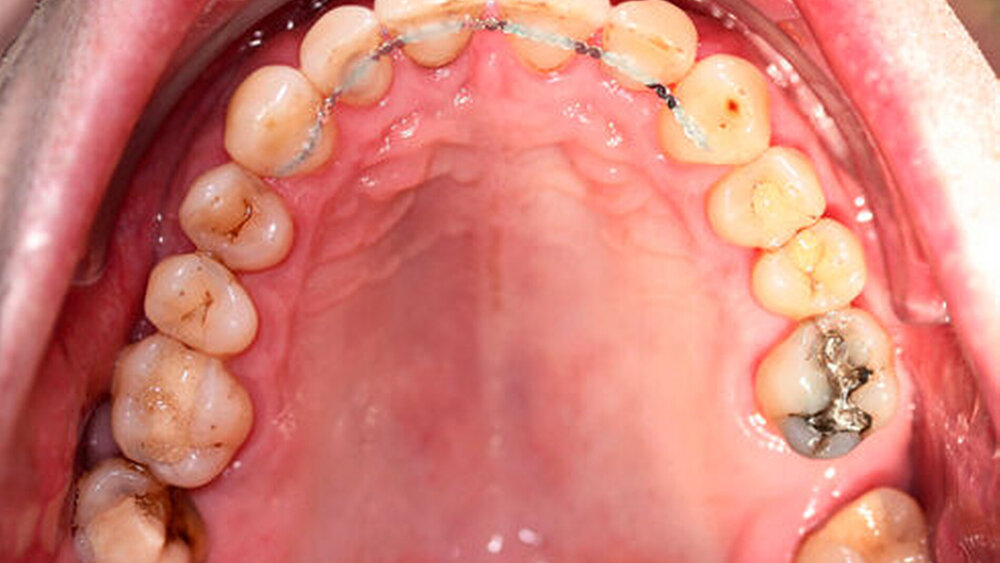

Röntgenologisch stellte sich im Orthopantomogramm der bereits intraoral ersichtliche horizontale und vertikale Knochenabbau mit Attachmentverlust an einzelnen Zähnen dar. Die Erhaltungswürdigkeit einzelner Zähne war aufgrund des starken Knochenverlustes beziehungsweise der Beeinträchtigung des Halteapparates als kritisch zu beurteilen.

Zudem wurde die Diagnose einer Parodontitis gestellt, die eine Rücküberweisung an den Hauszahnarzt erforderlich machte (Abbildung 2).